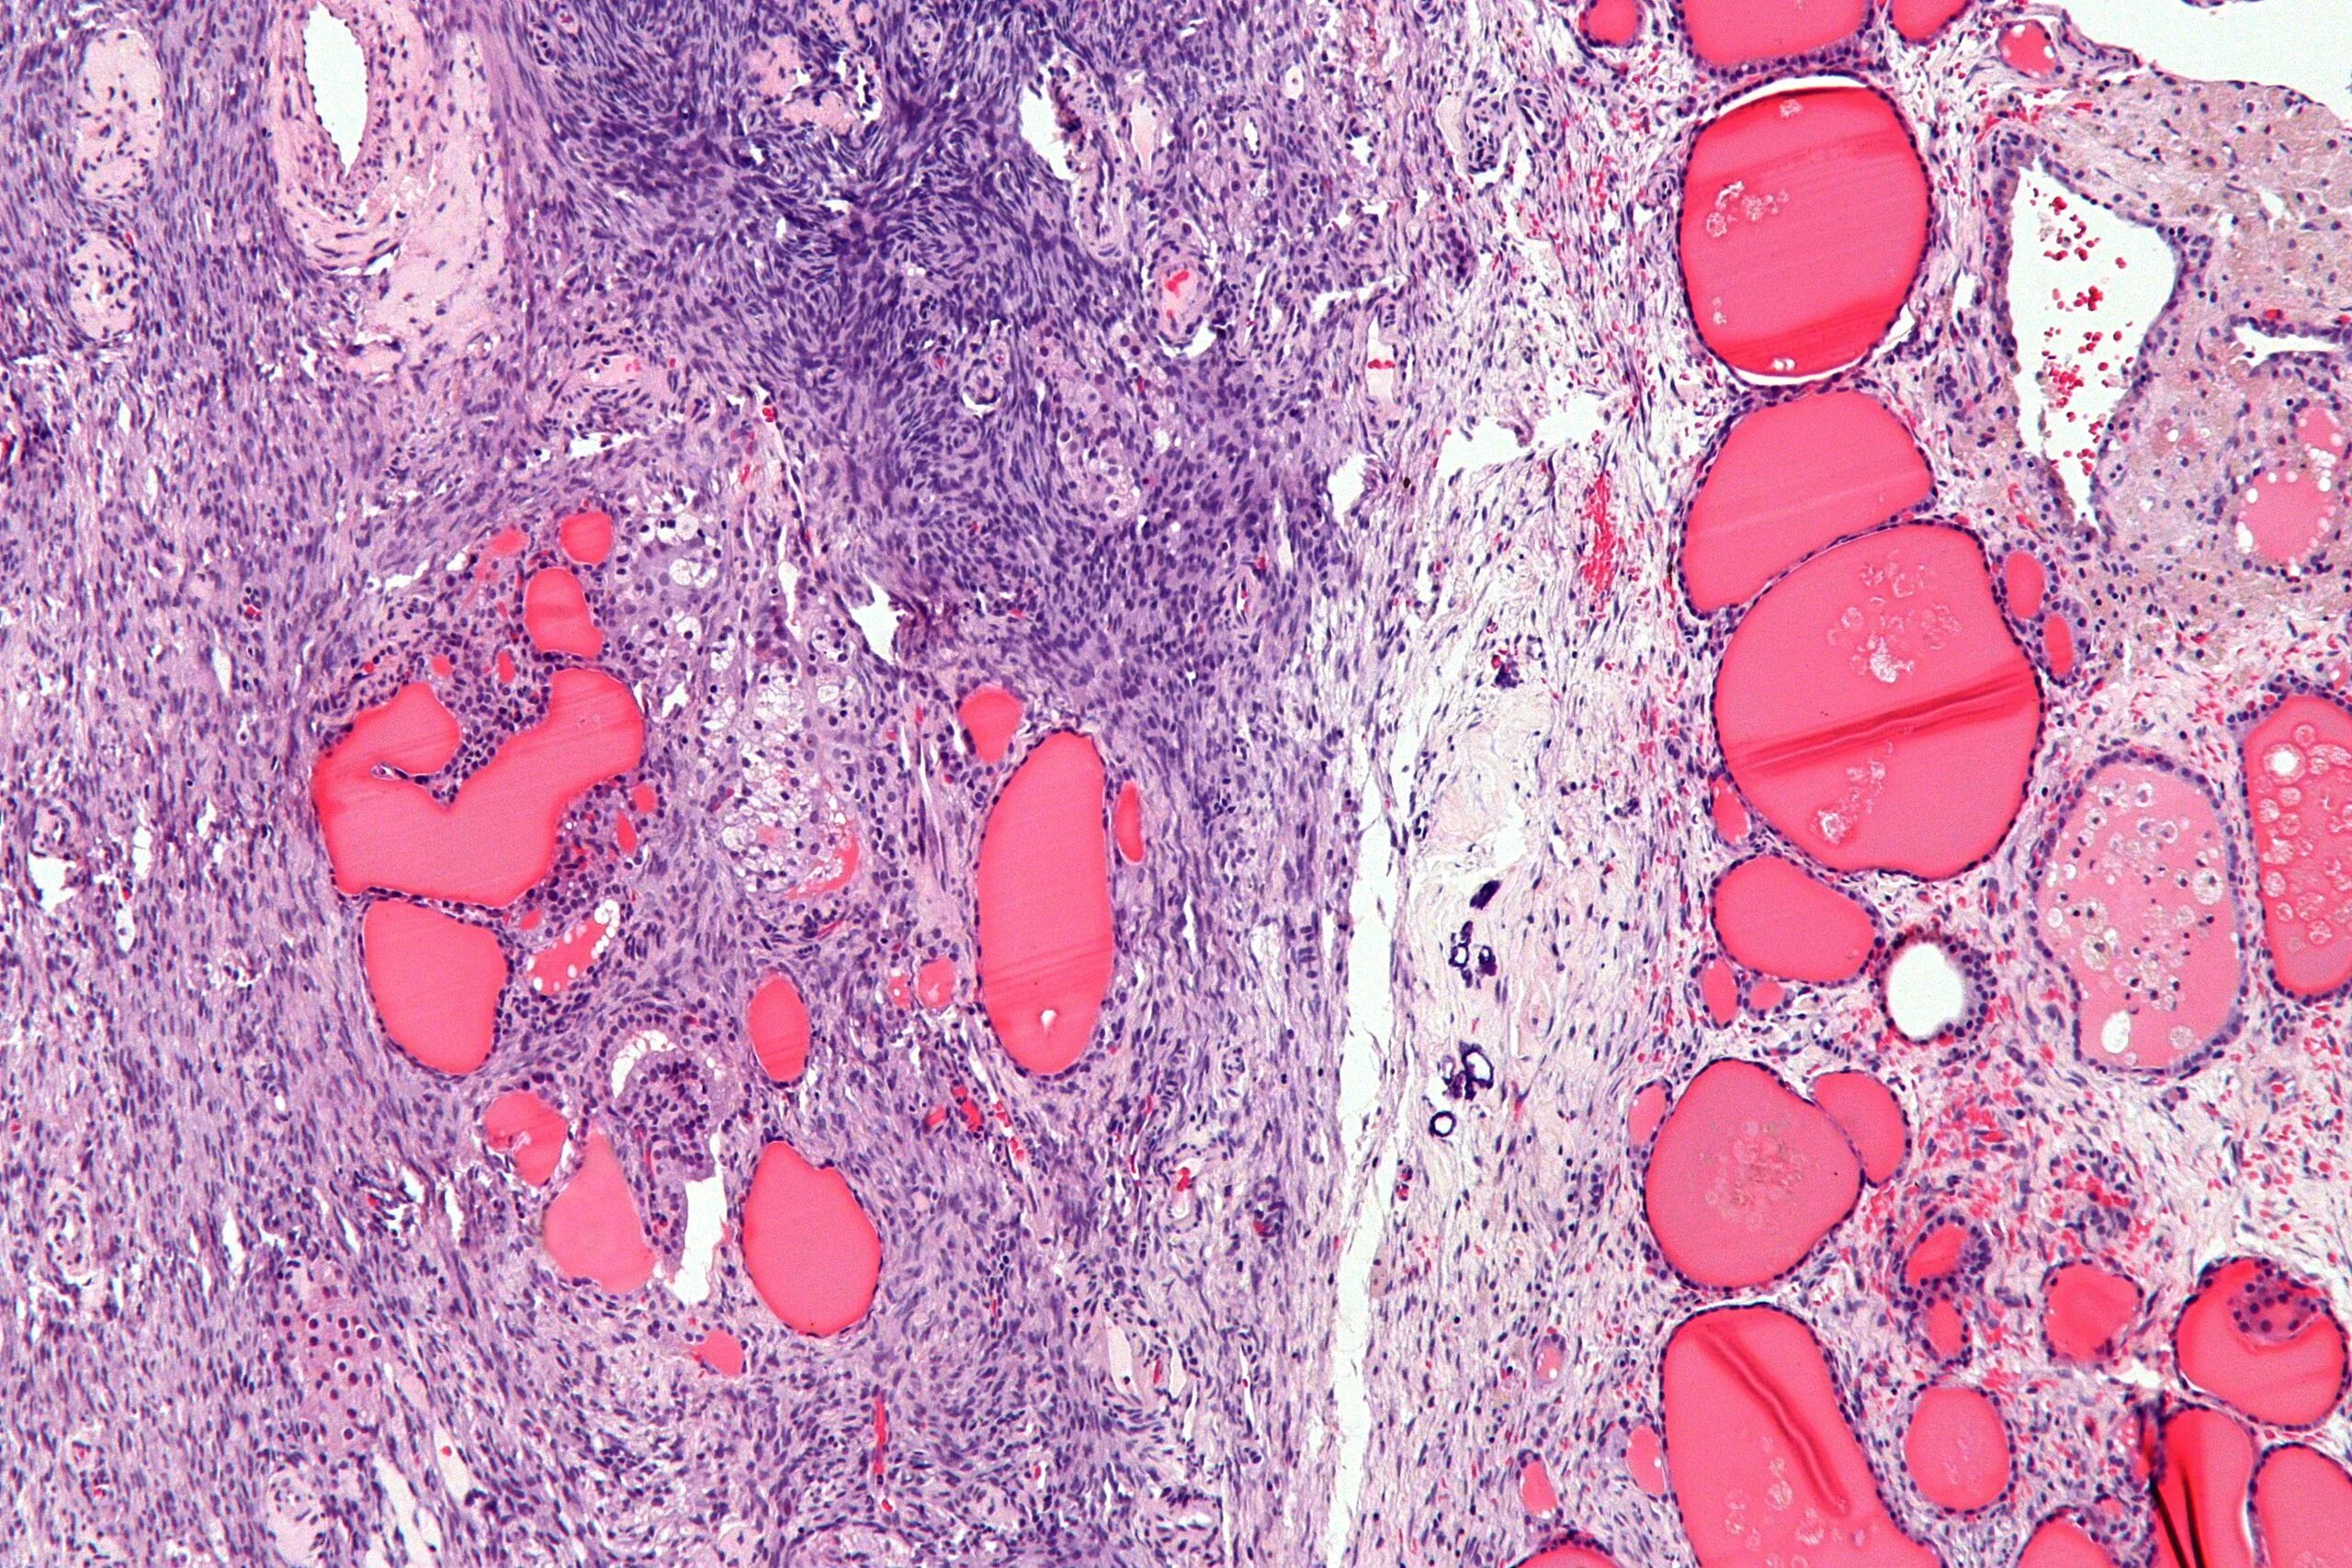

Опухоль с преобладанием стромы на ощупь